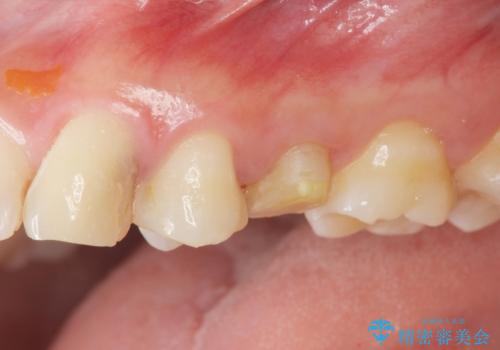

- 歯ぐきの腫れや、歯の内部が黒く見えることからの虫歯の治療を求めて来院されました。

虫歯が大きかったことから、神経の温存はできたものの歯ぐきよりも深い虫歯の問題を解決するため部分矯正治療を併用したセラミック治療を行うこととしました。

当初、歯ぐきよりも深い虫歯のぞんざいや、歯のポジションに問題がありましたがマルチブラケットを用いた部分矯正を行うことで適切な位置へと歯を移動させ、歯周環境を整えたセラミック治療を行うことができました。